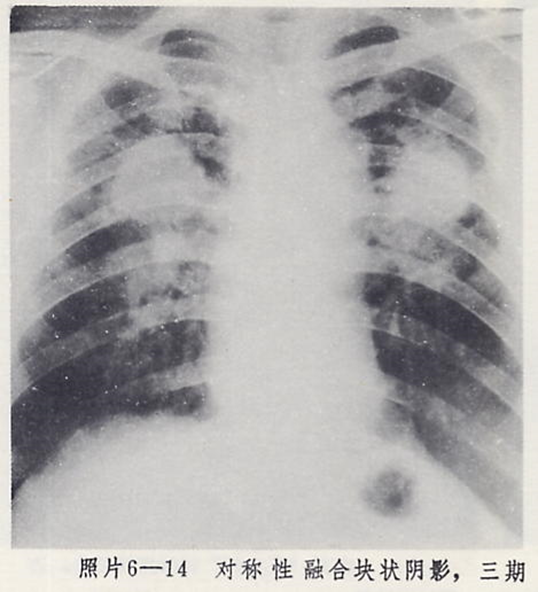

3)大阴影:在X射线胸片上,肺野内直径或宽度超过10mm的阴影,为晚期矽肺的重要X射线表现,形状有长条形、圆形、椭圆形、或不规则形,病理基础是团块状纤维化。大阴影的发展可由圆形小阴影增多、聚集,或不规则小阴影增粗、靠拢、重叠形成;多在两肺上区出现,逐渐融合成边缘较清楚、密度均匀一致的大阴影,常对称,形态多样,呈八字形等,也有先在一侧出现;大阴影周围一般有肺气肿带的X射线表现。

3)尘肺叁期:有下列表现之一者:

a) 有大阴影出现,其长径不小于20mm,短径不小于10mm;

b)有总体密集度为3级的小阴影,分布范围超过4个肺区并有小阴影聚集;

c) 有总体密集度为3级的小阴影,分布范围超过4个肺区并有大阴影。